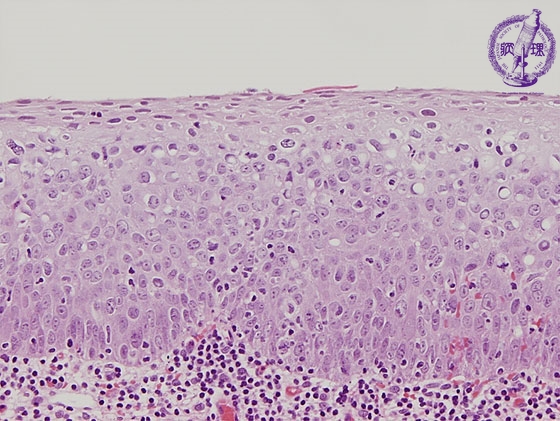

- ★(4)Cervical intraepithelial neoplasia

Histology (HE stain, high power): Severe dysplasia (CIN3). Atypical cells with nuclear enlargement, variable size of nuclei and high nuclear density proliferated from the side of basement membrane to more than 2/3 thickness of the epithelium.